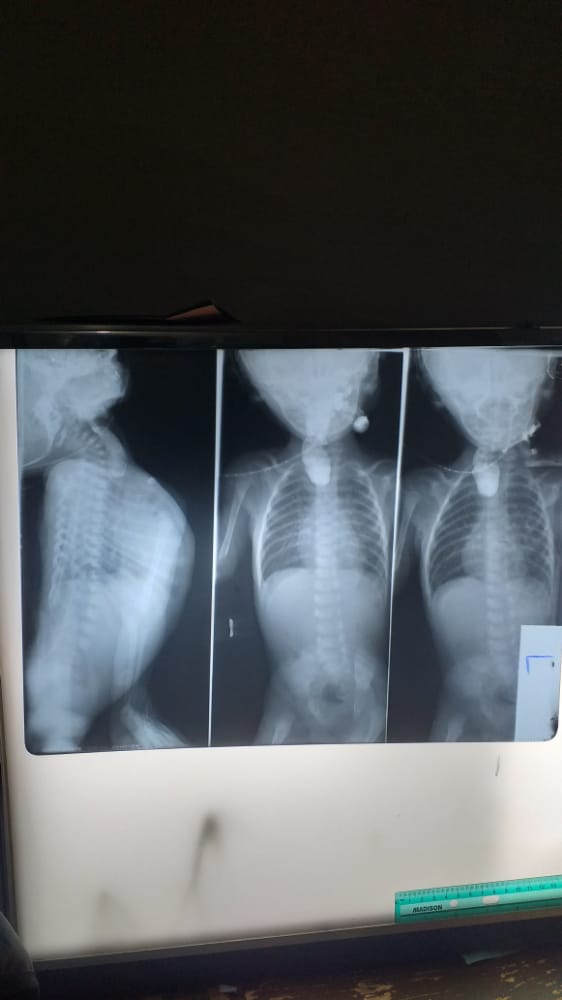

A contrast swallow (using low osmolar contrast medium: scanlux) was performed. This showed a blind ended esophagus with a pool of contrast medium (figures 3&4). The contrast was not demonstrated in the lung field. The distal esophagus and the stomach were also not contrast opacified. The vertebral spine showed normal appearances.

Figure 4: Anterior-posterior views of the contrast swallow demonstrating a proximal contrast filled pouch; the proximal esophageal atresia. Normal heart shadow, lung-fields, pockets of lucencies in the right and left hemi-diaphragms and pelvic region. Normal bones of the thoracic cage, vertebral spine and pelvic bones.